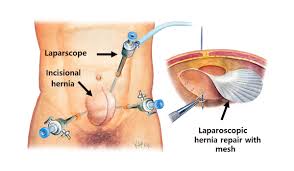

Overview

Package includes:

Days in hospital : 3 to 4 Days (For patient and one attendant)

Days in hotel : 15 Days (For patient and one attendant)

Room type in hospital : Shared

Room type in hotel : Private

Hotel category: Standard

Value added benefits of the Herniorrhaphy - Inguinal - Unilateral:

Ø Doctor consultation charges

Ø Lab tests and diagnostic charges

Ø Room charges inside hospital during the procedure

Ø Surgeon Fee

Ø Nursing charges

Ø Hospital surgery suite charges

Ø Anesthesia charges

Ø Routine medicines and routine consumables (bandages, dressings etc.)

Ø Food and Beverages inside hospital stay for patient and one attendant.

Overview

Package includes:

Days in hospital : 3 to 4 Days (For patient and one attendant)

Days in hotel : 15 Days (For patient and one attendant)

Room type in hospital : Shared

Room type in hotel : Private

Hotel category: Standard

Value added benefits of the Hernioplasty Inguinal with Mesh:

Ø Doctor consultation charges

Ø Lab tests and diagnostic charges

Ø Room charges inside hospital during the procedure

Ø Surgeon Fee

Ø Nursing charges

Ø Hospital surgery suite charges

Ø Anesthesia charges

Ø Routine medicines and routine consumables (bandages, dressings etc.)

Ø Food and Beverages inside hospital stay for patient and one attendant.

Overview

Package includes:

Days in hospital : 2 to 3 Days (For patient and one attendant)

Days in hotel : 15 Days (For patient and one attendant)

Room type in hospital : Shared

Room type in hotel : Private

Hotel category: Standard

Value added benefits of the Hernioplasty Inguinal Bilateral with mesh:

Ø Doctor consultation charges

Ø Lab tests and diagnostic charges

Ø Room charges inside hospital during the procedure

Ø Surgeon Fee

Ø Nursing charges

Ø Hospital surgery suite charges

Ø Anesthesia charges

Ø Routine medicines and routine consumables (bandages, dressings etc.)

Ø Food and Beverages inside hospital stay for patient and one attendant.